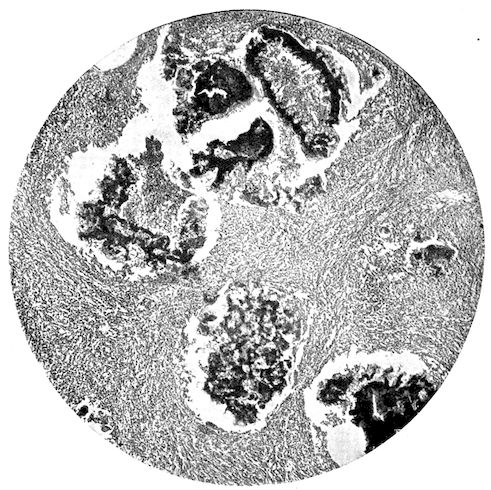

Fig. 1.—Rachitis in a young goat.